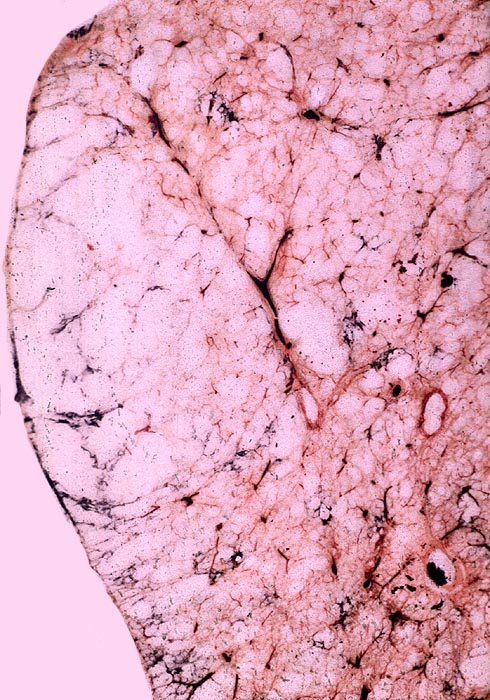

PathoPic ID 3598 - bullöses Randemphysem

bullöses Randemphysem

Lunge

Die Lunge weist grosse subpleural gelegene Löcher auf.

Makroskopie